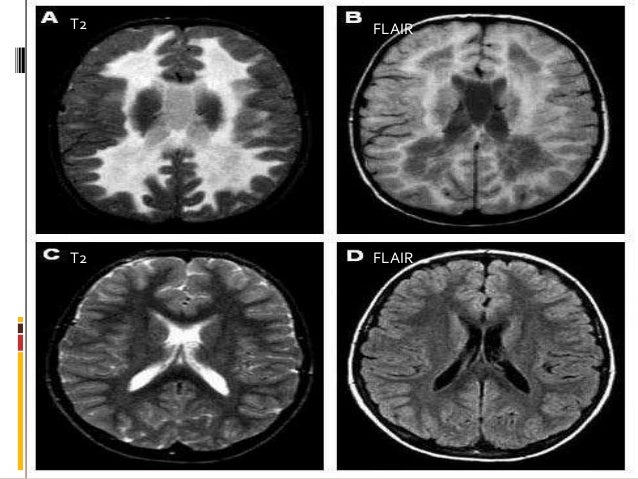

Demyelinated white matter lesions from MS and PML ...

Demyelinated white matter lesions from MS and PML ... from www.researchgate.net

White matter brain disorders typically result from abnormalities related to the myelin sheath. White matter is tissue that includes nerve fibers (axons) that said, some researchers have proposed a staging procedure for white matter lesions, which they suggest would help healthcare professionals. The researchers found that people with migraines ran a higher risk of brain lesions, abnormalities in brain white matter, and altered brain volume.

Although these are rightly viewed as more common with cortical lesions, recent research also links them with white matter damage. Mohamad habes, aristeidis sotiras, guray erus, jon objectives to investigate spatial heterogeneity of white matter lesions or hyperintensities (wmh). In older persons with white matter lesions, migraine is generally not invoked as a potential cause as there are ample other processes to blame. White matter lesions (wmls) or leukoaraiosis indicate small vessel vascular brain disease as well as degenerative or inflammatory processes.